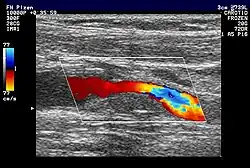

V lékařství (sonografie)

Ultrazvuk se dá použít třeba při lékařském vyšetření v lékařské ultrasonografii nebo echokardiografii. Ultrazvukové vlny o frekvenci 1 až 18 MHz procházejí tělem a odrážejí se od jednotlivých orgánů resp. od přechodů mezi tkáněmi s různou akustickou impedancí.

Slovníkové heslo ultrazvuk ve Wikislovníku- Informace o sonografii ve Fakultní nemocnici Plzeň na Klinice zobrazovacích metod naleznete zde